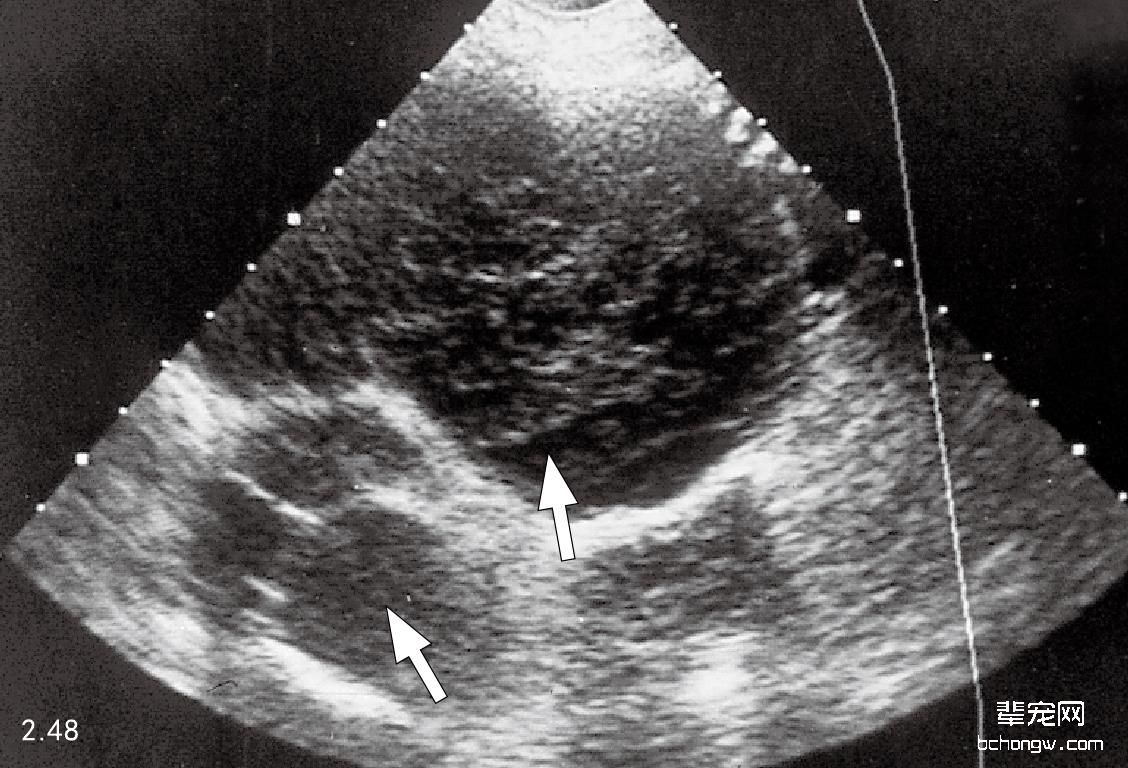

X线检查 侧面影像中,前部胸腔纵隔肿块引起气管偏离,心脏后侧移位和前侧心脏边缘消失;在背腹侧影 像中前部纵隔增宽和肺前叶后侧移位(图2.44和图2.45)。胸腔壁肿瘤通常引起软组织膨胀,导致邻近的肋骨移 位,作为额外的胸膜肿块延伸进入胸腔(图2.46和图2.47)。

图2.48 患有颅侧胸腔纵隔淋巴瘤的6岁大丹犬的胸部超声波图:小块次回 声肿块(箭头所示)。